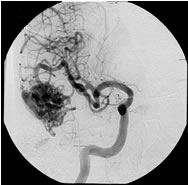

脳動静脈奇形

治療成績は病変の大きさ及び部位によって大きく異なりますが、直径3cm以内のガンマナイフ治療に適した脳動静脈奇形の場合、3年後の完全閉塞率(治癒率)は60−90%前後と報告されています。下図はガンマナイフ治療が奏功し、完全閉塞した典型的な症例です。

ガンマナイフ時の脳血管撮影

![]() |

| 正面像 | 側面像 |